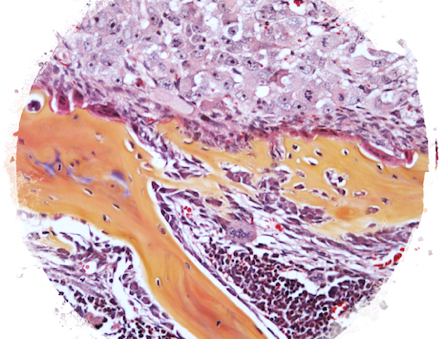

Growth Plate and Intervertebral Disc Development

We are interested in better understanding how cells in growth plates and intervertebral discs can actively proliferate and generate their rich extracellular matrix, while under hypoxia, low nutrient availability and hyperosmotic conditions.